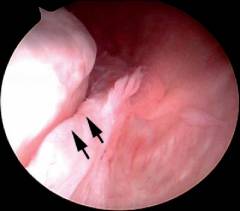

- Суставная губа. Головка плеча имеет шаровидную форму, а суставная впадина на лопатке – чашеобразную. Суставная губа, представляющая собой хрящ, обрамляет края впадины.

| Нестабильность плечевого сустава | Состояние, при котором связочный аппарат не удерживает головку плечевой кости. Это приводит к вывихам. Артроскопия может выявить повреждения суставной губы, капсулы, связок. |

- Суставная губа. Головка плеча имеет шаровидную форму, а суставная впадина лопатки напоминает чашу. Она небольшая и не охватывает головку полностью, поэтому дополнена суставной губой — хрящом, обрамляющим ее край.

| Нестабильность плечевого сустава | Это состояние, при котором связки не удерживают головку плечевой кости в суставной впадине, что приводит к вывихам и подвывихам. Артроскопия может обнаружить повреждения суставной губы, капсулы и связок. |